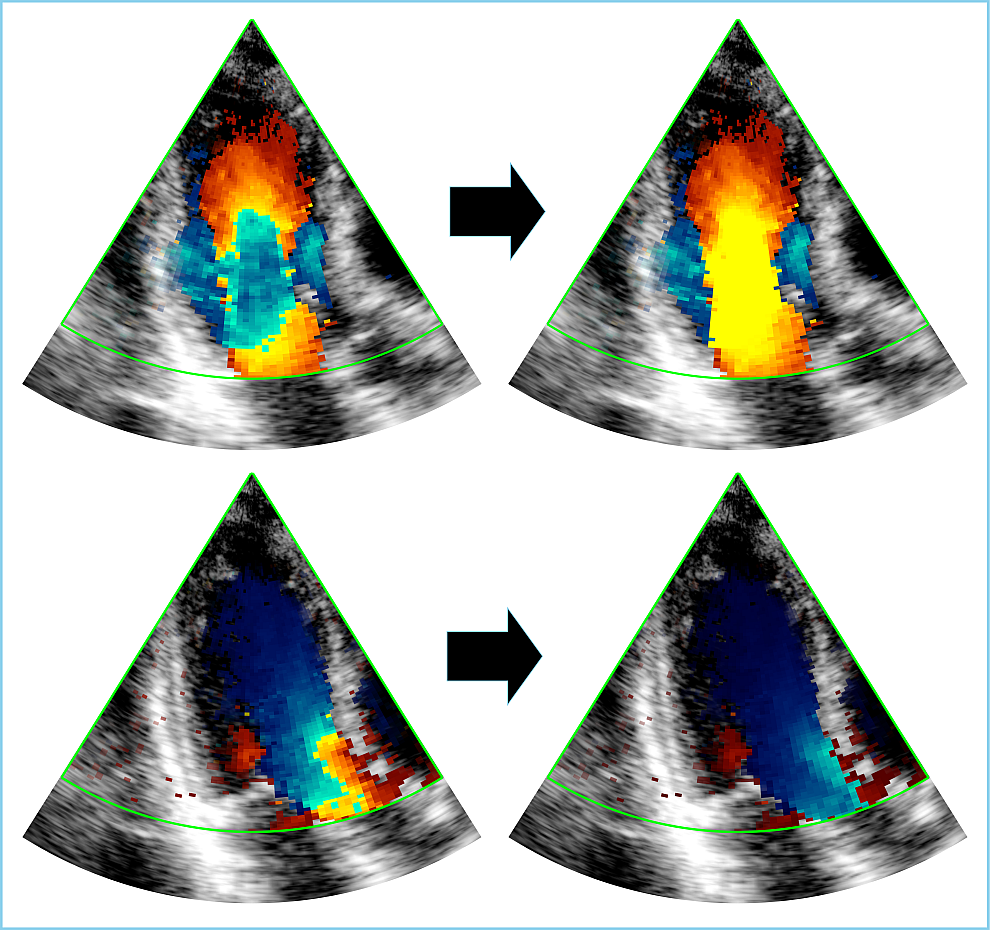

Color Doppler images may exhibit aliasing only in localized regions or frames, resulting in datasets that are often imbalanced, with most pixels belonging to the background class (i.e., without aliasing). To address this issue, we used standard data augmentation techniques such as rotation, flipping etc., during training. We also proposed an additional data augmentation technique, which we called artificial aliasing augmentation, to improve the generalizability of our algorithms. This technique involved identifying regions with high Doppler velocity and power on alias-free Doppler images, and applying a wrapping function defined by (3) with a lower Nyquist velocity to create artificial aliasing artifacts, followed by a normalization. The ground-truth references of these artificially aliased frames were created on the fly by comparing the Doppler velocities before and after this augmentation. By creating realistic artificially aliased frames, as shown in Fig. 2, this strategy enabled us to balance the classes in training batches. To evaluate the potential benefits of artificial aliasing augmentation, we conducted an additional ablation study where we tested the three DL models with and without this technique during training.

Refer to caption

Figure 2: Generation of synthetic images with artificial aliasing artifacts (right column) from non-aliased images (left column).